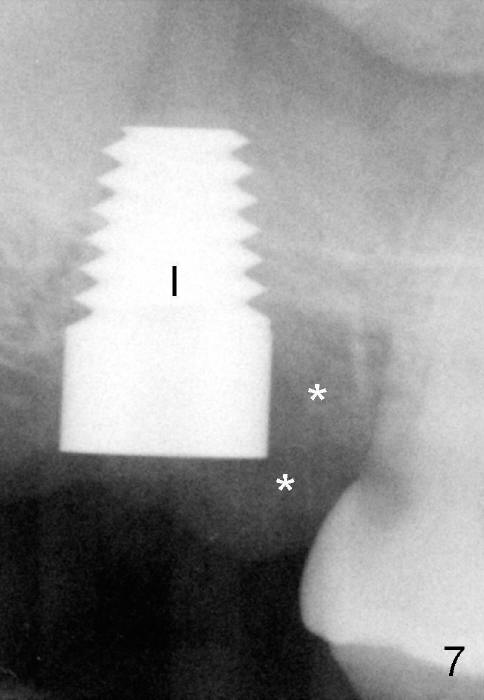

By contrast the palatal socket is deep and relatively small (Fig.4 P), easy to insert taps without drills. When a 7x11 mm tap is placed (Fig.5 T), the coronal end is more or less near the lingual cusps (functional cusps). Although the 7x14 mm tap (Fig.6 T) and a 7x11 mm implant (Fig.7 I) look poking into the maxillary sinus, they are in fact within the palatal socket (Fig.10c). Allograft and Osteogen are placed in the buccal socket (Fig.7 *), followed by collagen dressing (Fig.8 *). A 5x5 mm abutment is placed (Fig.8 A). An immediate provisional (Fig.9 P) is cemented to keep the graft and collagen dressing in place.